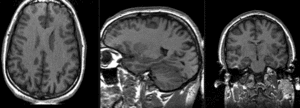

Registration Results

RegLib C10 unregistered.png unregistered (click to enlarge)

RegLib C10 registered1 Affine.png after affine registration (click to enlarge)

RegLib C10 registered2 Affine.gif after affine registration (click to enlarge)

RegLib C10 registered3 BSpline.gif after nonrigid BSpline (5x5x3) registration (click to enlarge)

RegLib C10 registered4 BSpline2.gif after nonrigid BSpline (7x7x5) registration (click to enlarge)